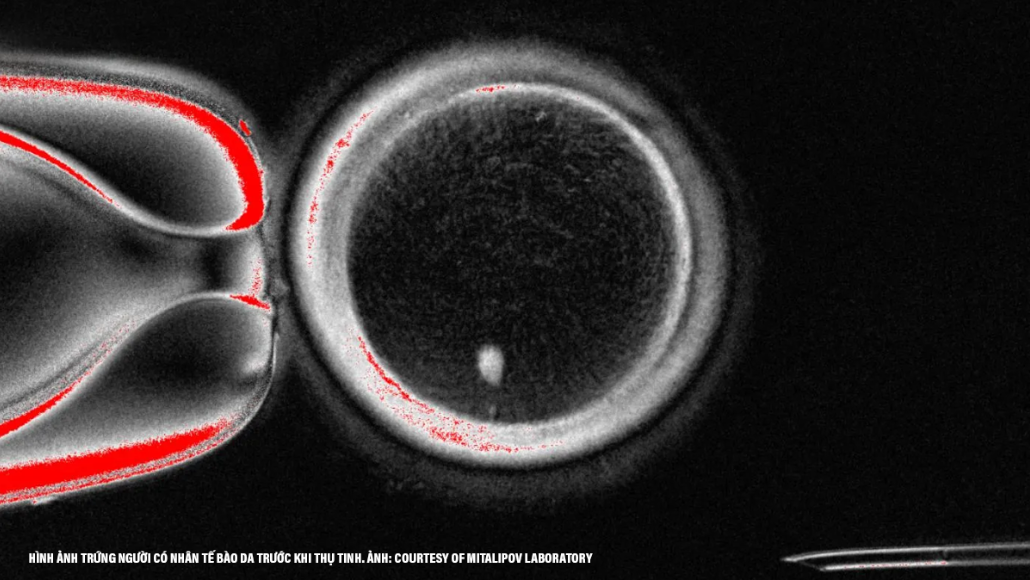

Old  Default Khoa học đã tạo ra trứng người từ tế bào da và đem sử dụng chúng để hình thành ra phôi thai

Các khoa học gia ở Mỹ vừa cho công bố ra một bước đột phá gây ra nhiều tranh cãi trong lãnh vực sinh sản: họ đã tạo ra trứng người từ tế bào da và thậm chí còn cho thụ tinh được để hình thành ra phôi thai ở giai đoạn sớm. Công trình này, do nhóm chuyên gia nghiên cứu tại Đại học Y khoa ở tiểu bang Oregon thực hiện và đăng tải lên tạp chí Nature Communications, mở ra triển vọng mới về một thế hệ kỹ thuật điều trị bệnh vô sinh mới, nhưng đồng thời kéo theo nhiều câu hỏi về mặt đạo đức.

Trong cuộc thí nghiệm, nhóm đã lấy nhân của tế bào da người và cấy vào một trứng được hiến tặng đã loại bỏ ra nhân. Kỹ thuật này gợi nhớ đến phương pháp từng tạo ra con cừu Dolly nổi tiếng hồi năm 1997. Sau đó, trứng được kích thích qua xung điện và thuốc để bắt chước quá trình cho giảm phân, nhằm loại bỏ bớt bộ nhiễm sắc thể. Kết quả, họ đã thu thập được 82 trứng có thể cho thụ tinh.